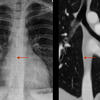

vessesls MR

Date: 02/25/2013

Views: 3221

normal vessels

Views: 3285